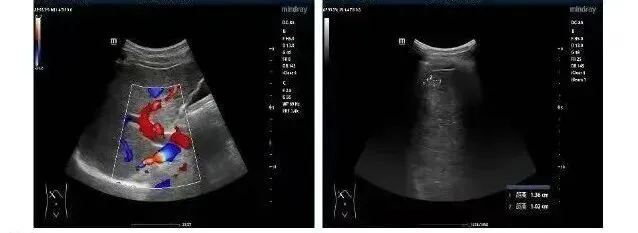

定期做腹部B超(或CT),如果检查结果显示:肝硬化的形态没有加重,没有长出新的异常结节,也没有新增腹水、脾脏肿大加重的情况;